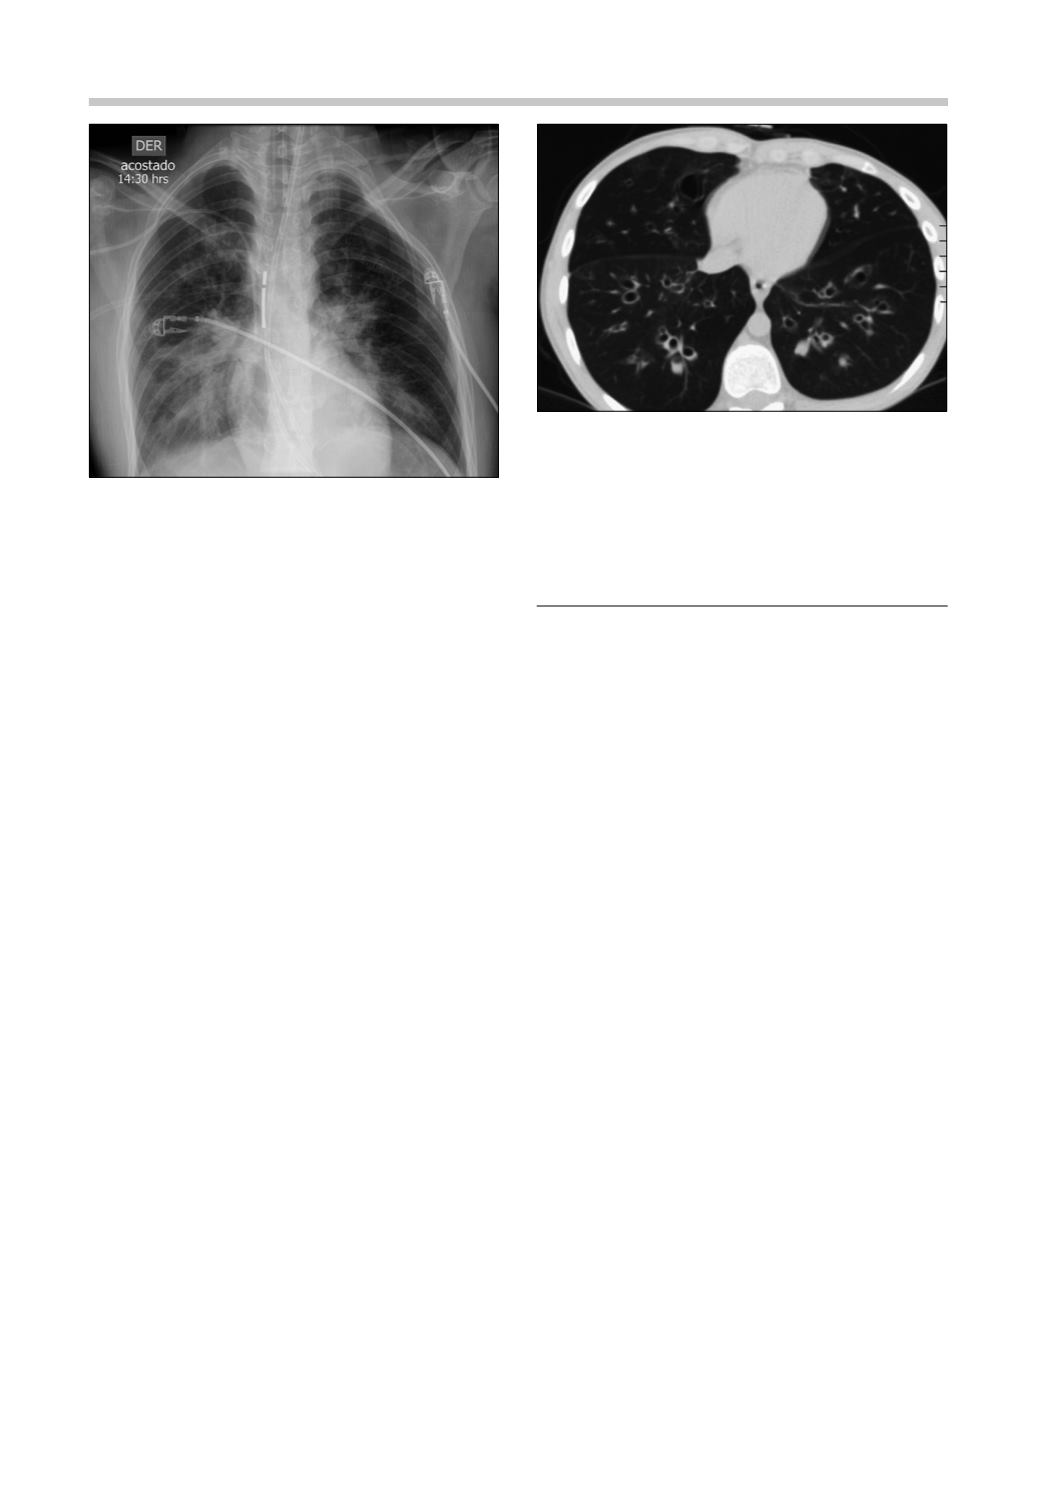

La Figura 4 muestra el compromiso pulmonar

al noveno mes de evolución.

Figura 4.

TAC de tórax al noveno mes de evolución.

Compromiso pulmonar difuso con zonas de vidrio esme-

rilado, patrón en mosaico, dilataciones y engrosamiento

de las paredes bronquiales.

Figura 3.

Radiografía de tórax al ingreso. Opacidades

pulmonares intersticio-alveolares perihiliares bilaterales.